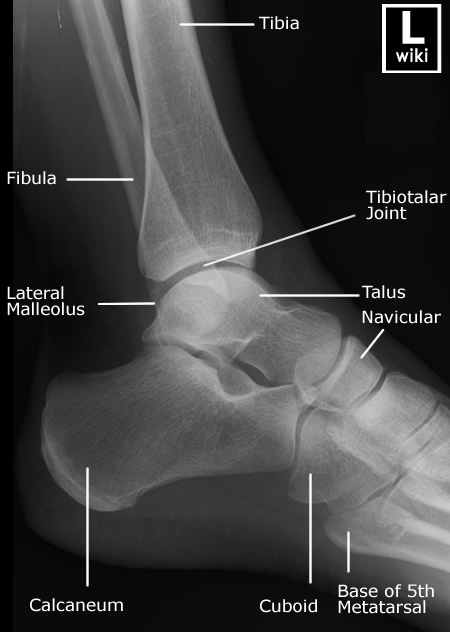

| [Anatomy] Ankle(발목) (0) | 2024.01.25 |